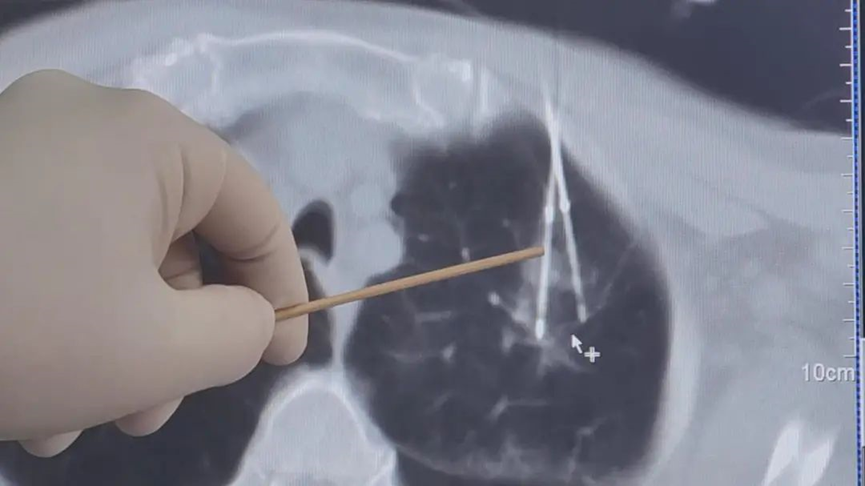

รายงานภาพก่อนผ่าตัด: ตุ่มเนื้อตั้งอยู่ในกลีบปอดซ้ายส่วนบน ใกล้กระดูกซี่โครงและเยื่อหุ้มปอด

ระหว่างขั้นตอนการรักษา

▲ เข็มความเย็น (Cryoablation) อันแรกถูกสอดเข้าไป โดยตุ่มเนื้อในปอดถูกกดลงอย่างนุ่มนวลเพื่อหลีกเลี่ยงการบาดเจ็บต่อเยื่อหุ้มปอดระหว่างการจี้เย็น

▲ เข็มอันที่สองถูกสอดตามมาและปรับมุมให้เหมาะสม จากนั้นทั้งสองเข็มถูกจัดให้อยู่ในตำแหน่งที่ลักษณะคล้าย "ตะเกียบ" เพื่อจับตุ่มเนื้อในปอดสำหรับการรักษา

▲ การสแกน CT แสดงให้เห็น "ก้อนน้ำแข็ง" ขนาด 4×3.3 ซม. ปกคลุมบริเวณปมอย่างสมบูรณ์ ในขณะที่ยังรักษาระยะห่าง 2 ซม. จากเยื่อหุ้มปอด เพื่อหลีกเลี่ยงอาการปวด